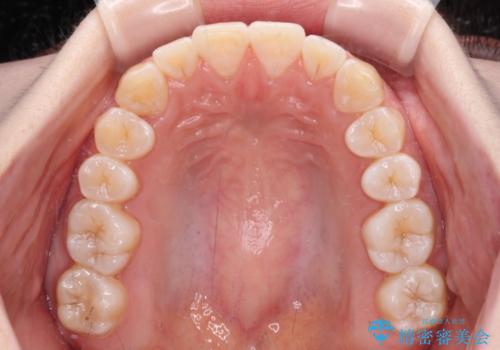

患者様も驚く、僅か10か月での治療終了となりました。

下顎前歯が1歯欠損しているため、上下正中は合わず、左右奥歯の咬み合わせは理想的とはならない仕上がりとなります。